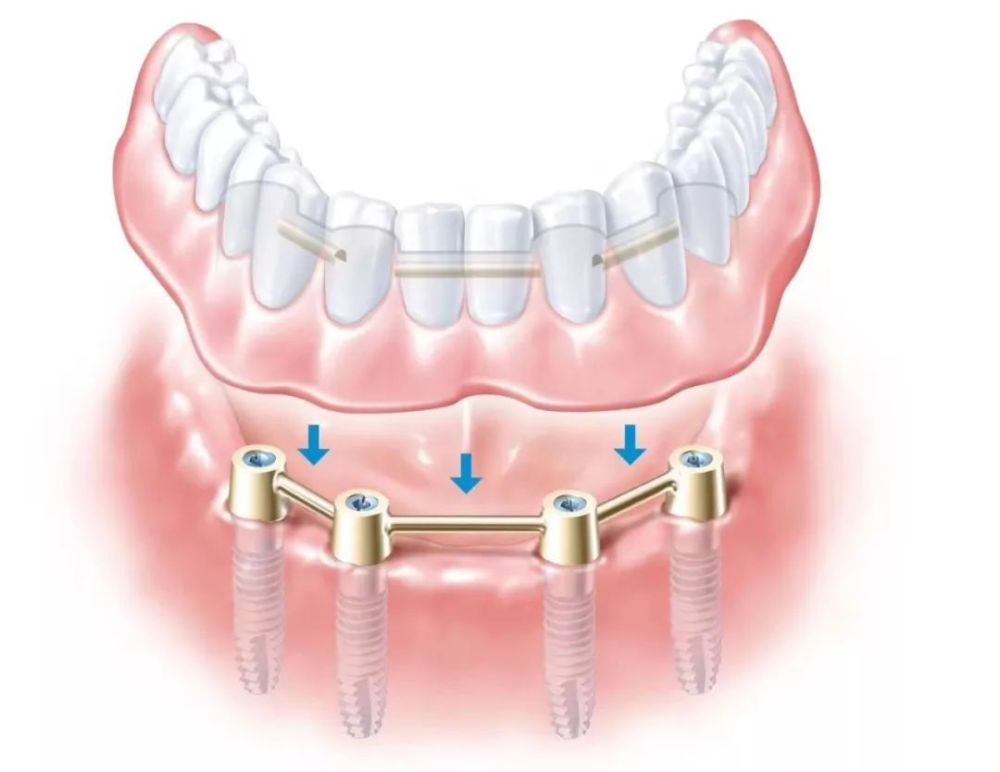

(All-on-4 全口/半口种植)

种植牙是医学界公认的理想修复方式,被誉为“人类的第三副牙”。相比活动假牙不舒服、难清洗、容易引起口腔黏膜病变,种植牙更稳固耐用,舒适美观,咀嚼功能好,一次种植,终生受用。种植牙不仅是中老年人的专利,年轻人因意外、牙病等造成牙齿缺失,也能够通过种植牙进行修复治疗,重获美丽笑容。